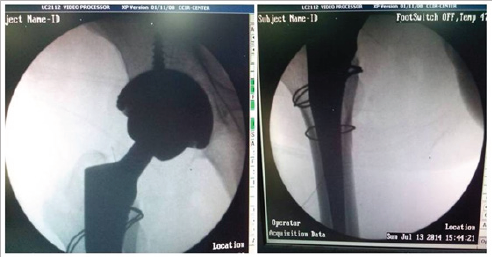

Figure 3(a).

Under general anesthesia, the patient was positioned laterally and a Moore's posterior approach was taken guided by dislocation and wall fracture. The gluteus maximus had a huge rent and external rotators were torn, the head was seen indenting the sciatic nerve (bowstring effect) which was contused but intact (Figure 3a). The neck was ostetomised with help of saw at the appropriate level and the calcar was reconstructed using encirclage wiring (Figure 3b). Ethibond was used to suture the greater trochanter. Next 2 temporary K wires were used in the ace tabular walls and reaming done and cement less cup size 52 was fixed augmented with 2 screws (Figure 3c). The K wires were removed after the cup was found stable. The femur was prepared and uncemeneted corail stem size 11 was inserted and size 36x0 femoral head was found stable. C arm was used to confirm the placement of implants (Figure 3d). All soft tissues were closed in best possible way, the hip was stable (Figure 3e). An abductor brace was applied post operatively. Postoperatively day one faradic stimulation was started and patient was allowed side tuning. Check X ray was done which showed a reasonable reconstruction (Figure 4). The patient was allowed sitting with non weight bearing mobilization from day 3 after the pain had subsided. 3 weeks after surgery the patient was discharged when he went back to his home state and never came back for follow up.

Figure 3(b).

Figure 3(c).

Figure 3(d).

Figure 3(e).